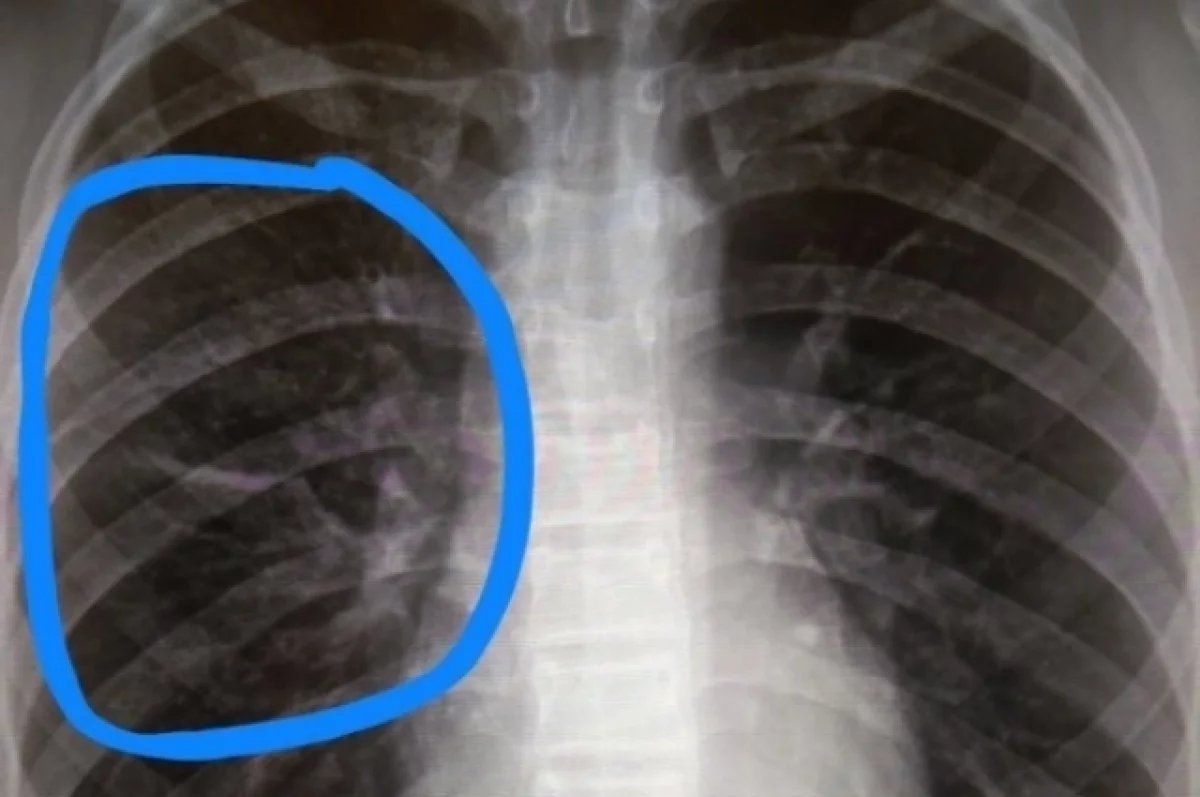

С начала года врачи выявили рак лёгких у 639 жителей Удмуртии

Врачи с начала года выявили рак лёгких у 639 жителей региона, сообщает пресс-служба минздрава Удмуртии.

В ведомстве отмечают: в половине случаев злокачественные образования диагностируются на поздних стадиях. Онкологи подчёркивают, что чаще всего заболевание выявляется у мужчин.

«Опасность рака лёгких в том, что явные внешние симптомы проявляются только на поздних стадиях. Это длительный кашель, боли в груди, кровохарканье, одышка с нарушением ритма и частоты дыхания, отёк лица и верхних конечностей, потеря веса без видимой причины», — рассказала заместитель главврача по медицинской части Республиканского онкодиспансера Светлана Лысанова.